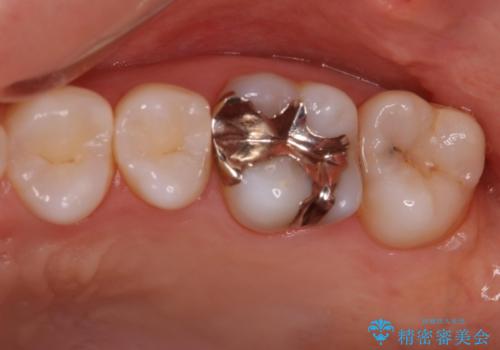

- 矯正しモチベーションが高くこの際メタルフリーにしたいという主訴で来られた患者様です。

検査してみたところ、後ろの歯も虫歯があったので治療させていただくことになりました。

左上奥歯2本治療することになりました。